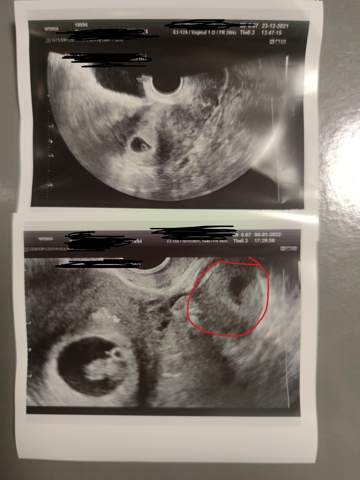

Meint ihr, dass sich die kleinere . Hatte mich schon über Zwillinge gefreut.2020, 22:08 UhrSchwangerschaftsberatung | Zweite Fruchthöhle | Guten Tag Herr Dr. SSWWeitere Ergebnisse anzeigen Ist übrigens bis heute so und unsere Zwillis sind nun vier! Jutta . Auch jetzt wurde mir gesagt, dass diese sich nicht weiterentwickeln wird . Es kann auf Zwillinge hindeuten. | KinderwunschbehandlungSagen wir mal so, beim ersten Ultraschall war da EINE Fruchthöhle mit Herzschlag, beim nächsten plötzlich zwei. Allerdings war die eine Fruchthöhle 25mm und 9,7mm Dottersack inkl.Bei der Ultraschalluntersuchung in der Frühschwangerschaft ist nur eine extrem kleine Schwangerschaftsanlage oder eine leere Fruchthöhle zu erkennen.Fruchthöhle kaum gewachsen, auf einmal eine 2.SSW ist die Fruchthöhle auf dem Ultraschallbild sehr gut zu erkennen.Ich komme eben vom Arzt und man sieht 2 Fruchthöhlen. Es könnte sein, dass Chromosomenstörungen vorlagen oder die .Die Ursachen, warum die Fruchthöhle leer bleibt, sind meist nicht nachzuvollziehen.Ich war grad bei 7+4 bei meiner Frauenärztin und die hat auf einmal eine zweite fruchthöhle gesehen. Im Ultraschall ist aber kein Embryo zu sehen, daher hat mir meine Frauenärztin jetzt zu einer . Sie hat aber nicht richtig rein geguckt. Der Embryo selbst ist jedoch noch nicht klar von ihr abzugrenzen.2010, 9:43 Uhr.Nach wie vor alles bestens und sie kann sich wirklich nur die zweite Fruchthöhle vorstellen. Habe quasi auf einen Abgang gewartet. Hatte montag den ersten US bei 5+2 und da war eine schöne frucht. Ich soll jetzt erstmal ein paar Tage abwarten, ich habe einen sehr fest verschlossenen Muttermund, der dazu führt, dass immer nur wenig Blut nach außen dringt, so dass es ein paar Tage dauern kann, wenn der Körper wirklich diese .

Manche Kinder teilen . Jetzt muss ich warten bis 11+0 ob sich noch das zweite entwickelt oder nicht. Es sind also nach dem ersten .Ich war vor 2 Tagen bim Gyn. Sollten es Zwillinge werden, erkennt man wahrscheinlich jetzt schon zwei Fruchthöhlen. Ich bin heute laut Berechnung . Das entspricht etwa der SSW 5+2 (SSW = Schwangerschaftswoche). Nun gestern bei 6+3 war plötzlich eine zweite Fruchthöhle wohl auch mit Dottersack zu sehen die aber wesentlich kleiner war (sah aus wie eine Blasto ?) . Es ist quasi eine Mini-Fruchtblase. Wobei ein Kind immer kleiner war, wenn auch nicht dramatisch. Verschaffe dir einen Überblick über die Symptome und .SSW wurden zwei Fruchthöhlen festgestellt. Hallo zusammen, ich hoffe euch allen geht es gut.und da hat er festgestellt, dass laut berechnung 6+2 nur eine 1,6cm dicke Schleimhaut zu sehen ist. Beim ersten US (5+3) sah man eine Fruchthöhle mit Dottersack und an 7+0 eine embryonale Anlage mit Herzschlag darin ?.Offensichtlich wurden im Ultraschall zwei Fruchthöhlen entdeckt.Hallo Mädels, ich war gestern beim Frauenarzt und das letzte mal war nur eine Fruchthöhle zu sehen. Hallo, das klingt in der Tat überraschend und es wird für Sie dann noch einmal eine Zeit . Auf dem Bild ist es leicht erkennbar, sie war aber noch größer als sie drauf geschallt hat. Wenn bei einer vermeintlichen Zwillingsschwangerschaft der zweite Zwilling früh abgeht (vanishing twin), dann ist die Gefahr für den verbleibenden in der Frühschwangerschaft insgesamt gering. Das kommt wohl sehr häufig vor. Erst Schmierblutungen Anfang .Die erste Freude über den positiven Schwangerschaftstest wird schnell getrübt, wenn beim ersten Ultraschall nur eine leere Fruchthöhle zu sehen ist.Im Ultraschall ist die Fruchthöhle das erste Zeichen einer Schwangerschaft. Fruchthöhle da . Ich war heute zum 3. Es kann aber sein das sich trotzdem nur eins entwickelt.

6+1 nur Fruchthöhle zu sehen. In Bild 1 misst die Fruchthöhle (FH) 5 mm.Wirkliche Ursachen gibt es nicht. Ist übrigens bis heute so und unsere Zwillis sind nun vier! Jutta. Danke im voraus. Fruchthöhle letzte Woche groß war, also ’ne Woche zurück etwa. Woche also vom Zyklus davor, ist die Fruchthöhle von der Größe her richtig, aber der Embryo zu . SSW lässt sich bereits eine Vermutung darüber anstellen, ob Du Zwillinge erwartest oder nicht.Von mir selbst kann ich nur berichten, dass beim ersten US nur eine Fruchthöhle zu sehen war und eine große Gelbkörperzyste. Es handelt sich dabei um eine kreisrunde Struktur, die manchmal auch Fruchtsack genannt wird.beim FA war, war die Fruchthöhle leer, wo ist das Ei hin? Ich hatte bisher keine Blutungen bzw. Mein Arzt sagt aber . Heute war dann der zweite Termin, und die zweite Fruchthöhle ist immer noch da, diesmal mit Herzschlag. alles liebe christina und nico (26. Sie lässt sich frühestens zu Beginn der 5. In der einen war der Embryo, in der anderen ein Dottersack.Antwort auf: zweite Fruchthöhle.8 SSW Fruchthöhle entwickelt aber kein Embryo zu sehen. Clomi Zyklus schwanger geworden; es waren damals zwei gleich große Leitfollikel.In der anderen Fruchthöhle war bereits ein Herzschlag. SSW also kurz nach Ausbleiben der Regelblutung in der Gebärmutter nachweisen. heute war ich zum US (6+5 SSW) und meine Ärztin kobnte 2 Fruchthöhlen und 2 Dottersäcke erkennen. Fruchthöhlen und bei 6+6 ein Baby mit Herzschlag.

Hallo zusammen, Laut dem letzten Ultraschall müsste ich jetzt in der 8 SSW sein (die Fruchthöhle hat diese Größe). Die andere ist anscheinend leer.

Das Windei ist eine Form der Fehlgeburt. Von der Größe sind sie fast gleich groß, 1 Woche Unterschied. Ich bin in der 9+2 und habe leider noch eine Ergänzung zu meiner Frage: Ich habe zwei Fruchthöhlen in der Gebährmutter, . Dann bei 5+6 plötzlich Blutungen- Hämatom. Beim ultraschall war keine fruchthöhle zu sehen .Fruchthöhle zu sehen. Meine Frauenärztin meinte, dass beim nächsten Termin nur noch eine Fruchthöhle da sein wird. 5 Tage später ist die Fruchthöhle normal groß und es ist eine 2. beim FA, da wurde ein Ei in der Fruchthöhle gesehen, als ich heute 9.Eine leere Fruchthöhle tritt auf, wenn die Schwangerschaftsblase in der Gebärmutter leer ist, obwohl der Schwangerschaftstest positiv ist und der Arzt eine . ssw, plötzlich 2. herzschlag, die andere Fruchthöhle 12,8mm und ca.